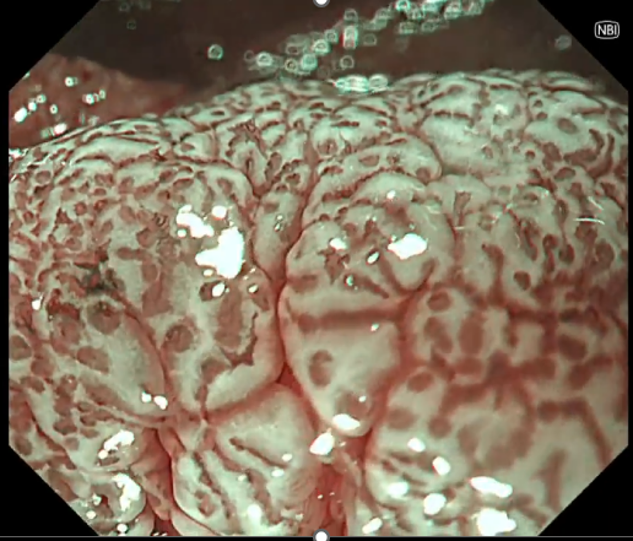

十二指腸腸型腺腫の拡大画像

NBI(左)に比べてNBI+TXI(右)ではWOSの形態が明瞭化している